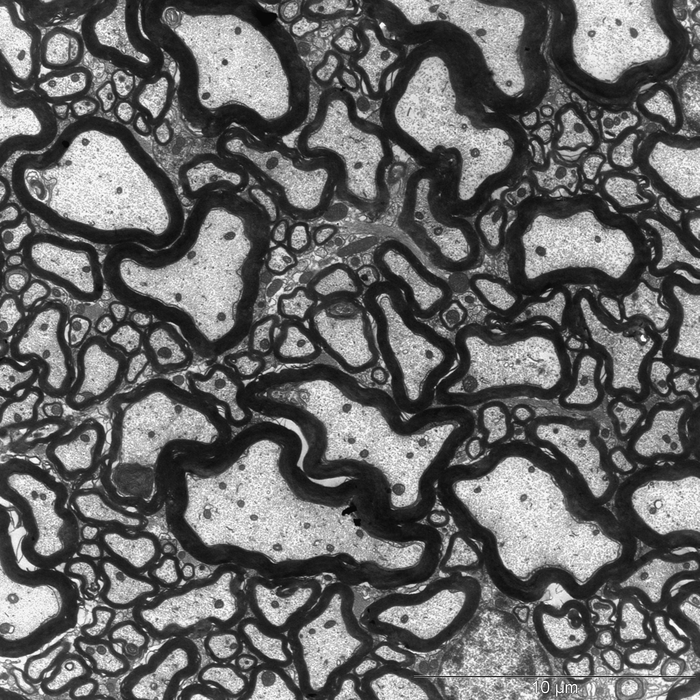

图片:在健康的小鼠体内,绝缘的髓磷脂(黑色)紧密地包裹在神经纤维(轴突)周围。

研究人员确实找到了他们想要寻找的东西:当他们将牛奶成分酪蛋白和一种效果增强剂一起给小鼠服用时,小鼠继续出现了神经紊乱。电子显微镜显示神经纤维周围的绝缘层,即髓鞘受损。这种脂肪状物质可以防止短路,并显著加速刺激传导。